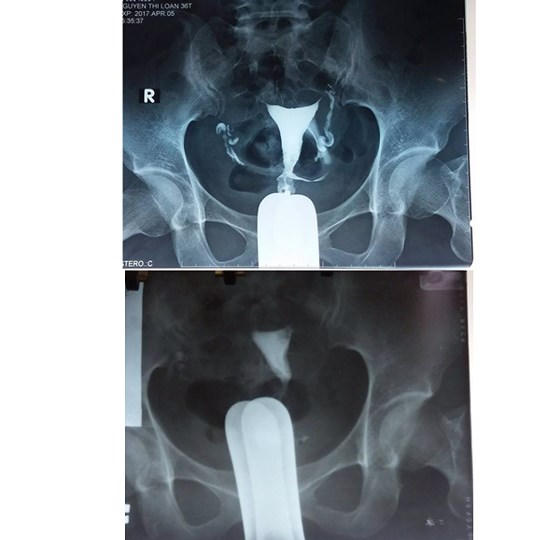

Đầu tháng 4/2017, lần đầu tiên, BV Phụ sản T.Ư công bố nghiên cứu và áp dụng thành công phương pháp chữa vô sinh mới đó là kỹ thuật “Nong vòi tử cung bằng catheter qua nội soi buồng tử cung kết hợp với nội soi ổ bụng”. Bênh nhân đầu tiên là chị Nguyễn Thị Loan (huyện Nghi Lộc, tỉnh Nghệ An), vô sinh thứ phát 8 năm do tắc vòi tử cung.

Vòi trứng bị tắc (ảnh trên) và vòi trứng đã được nong (ảnh dưới)

Do đó, với kỹ thuật mới nói trên, lần đầu tiên áp dụng tại Việt Nam, sẽ giúp cho nhiều phụ nữ hiếm muộn được làm mẹ với chi phí rất thấp. Hơn nữa, kỹ thuật này có thể chuyển giao cho các cơ sở khám chữa bệnh khác để bệnh nhân bị bệnh tắc vòi trứng, nhất là ở đoạn kẽ, có cơ hội được phẫu thuật để mang thai tự nhiên.